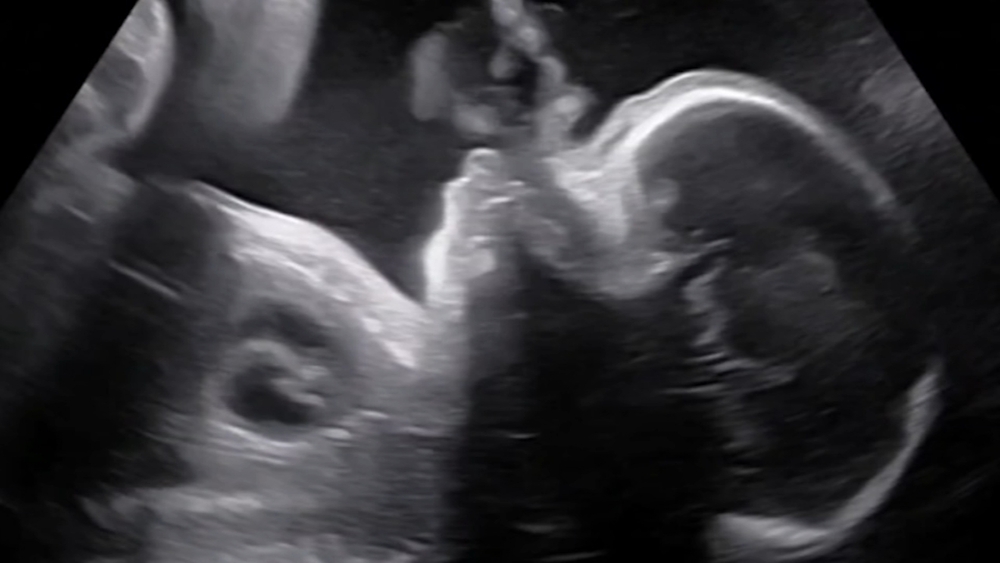

At the time, her unborn child, Juan Manuel Rivera Jr., was diagnosed with hypoplastic left heart syndrome in the womb.